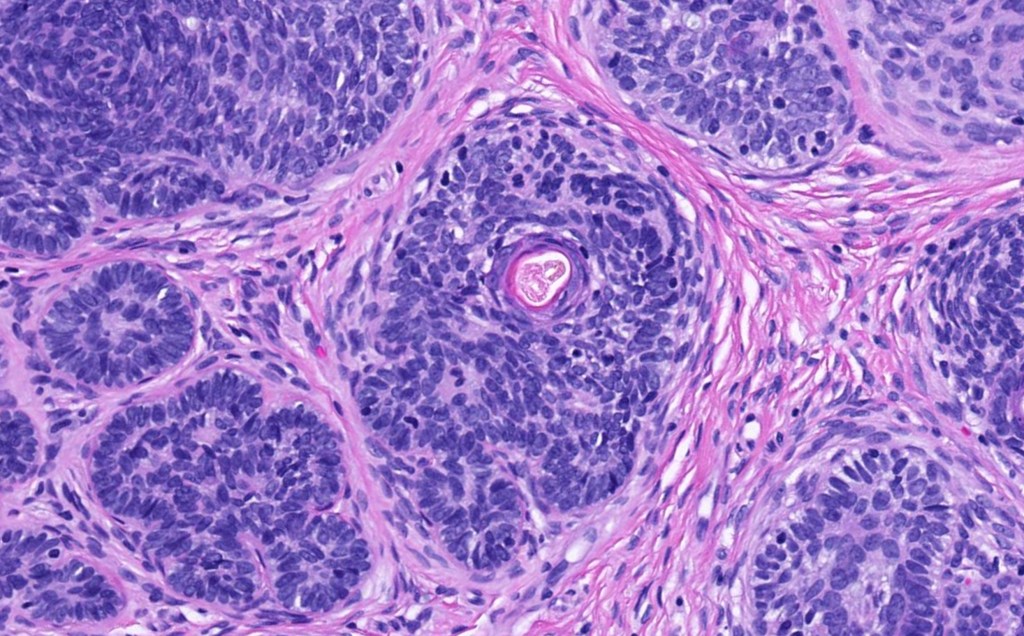

•Perifollicular mesenchyme is always conspicuous and sometimes densely aggregated are seen indenting the baslaloid lobules (papillary mesenchymal bodies)

Trichoepithelioma should be distinguished from trichoblastoma since the latter is very rarely syndromic. Trichoepithelioma is largely a dermal tumor whereas trichoblastoma often extends from the dermis into subcutaneous fat or deeper in very large examples. Papillary mesenchymal bodies are much better formed and generally more obvious in trichoepithelioma. Trichoepithelioma must also be distinguished from basal cell carcinoma. Retraction artifact & stromal mucin are features of basal cell carcinoma and not trichoepithelioma. Papillary mesenchymal bodies are not seen in basal cell carcinoma.